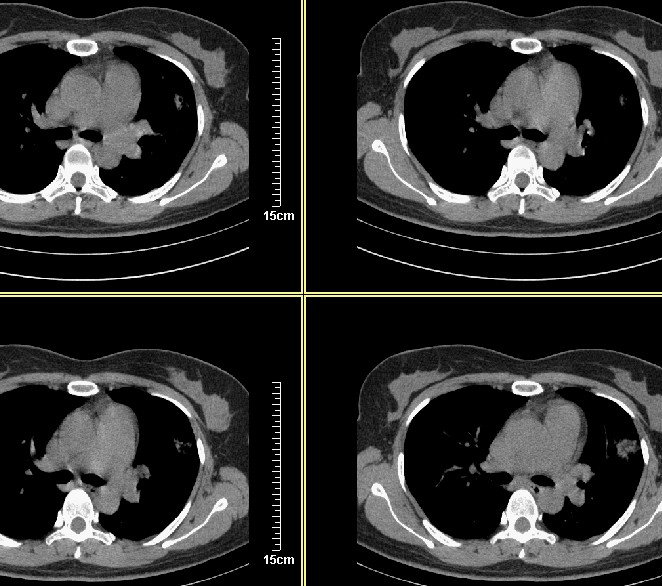

应该能确定是恶性病变,三天前周围出现的淡薄景应该是肺泡内积血

3天后复查:病变明显好转、吸收:考虑炎症可能性大

支气管注药后3天后复查:病变明显好转、吸收:考虑炎症可能性大.

能不能说说当时灌注的都是什么药吗? 不过从现在的片子看 还是考虑肿瘤    并肺门淋巴结转移

病变密度高实变率高不能排除肺癌